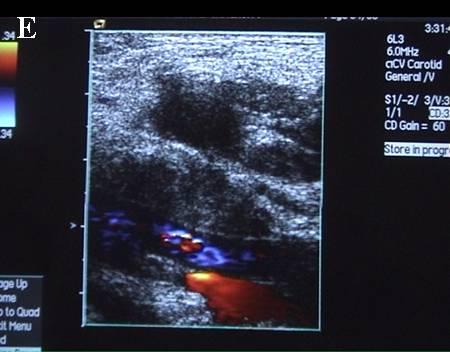

A 连接三联管及穿刺针准备 B 超声引导下注射针进入瘤腔底部(箭头处) C 经注射针注入盐水出现超声频闪现象; D 远端瘤腔内血栓逐渐形成; E 远端、近端瘤腔内血栓完全形成; F 术后足背动脉血流良好. 国内首家开展,例数最多,疗效肯定。此技术在全国推广应用。处于全国领先水平。 |